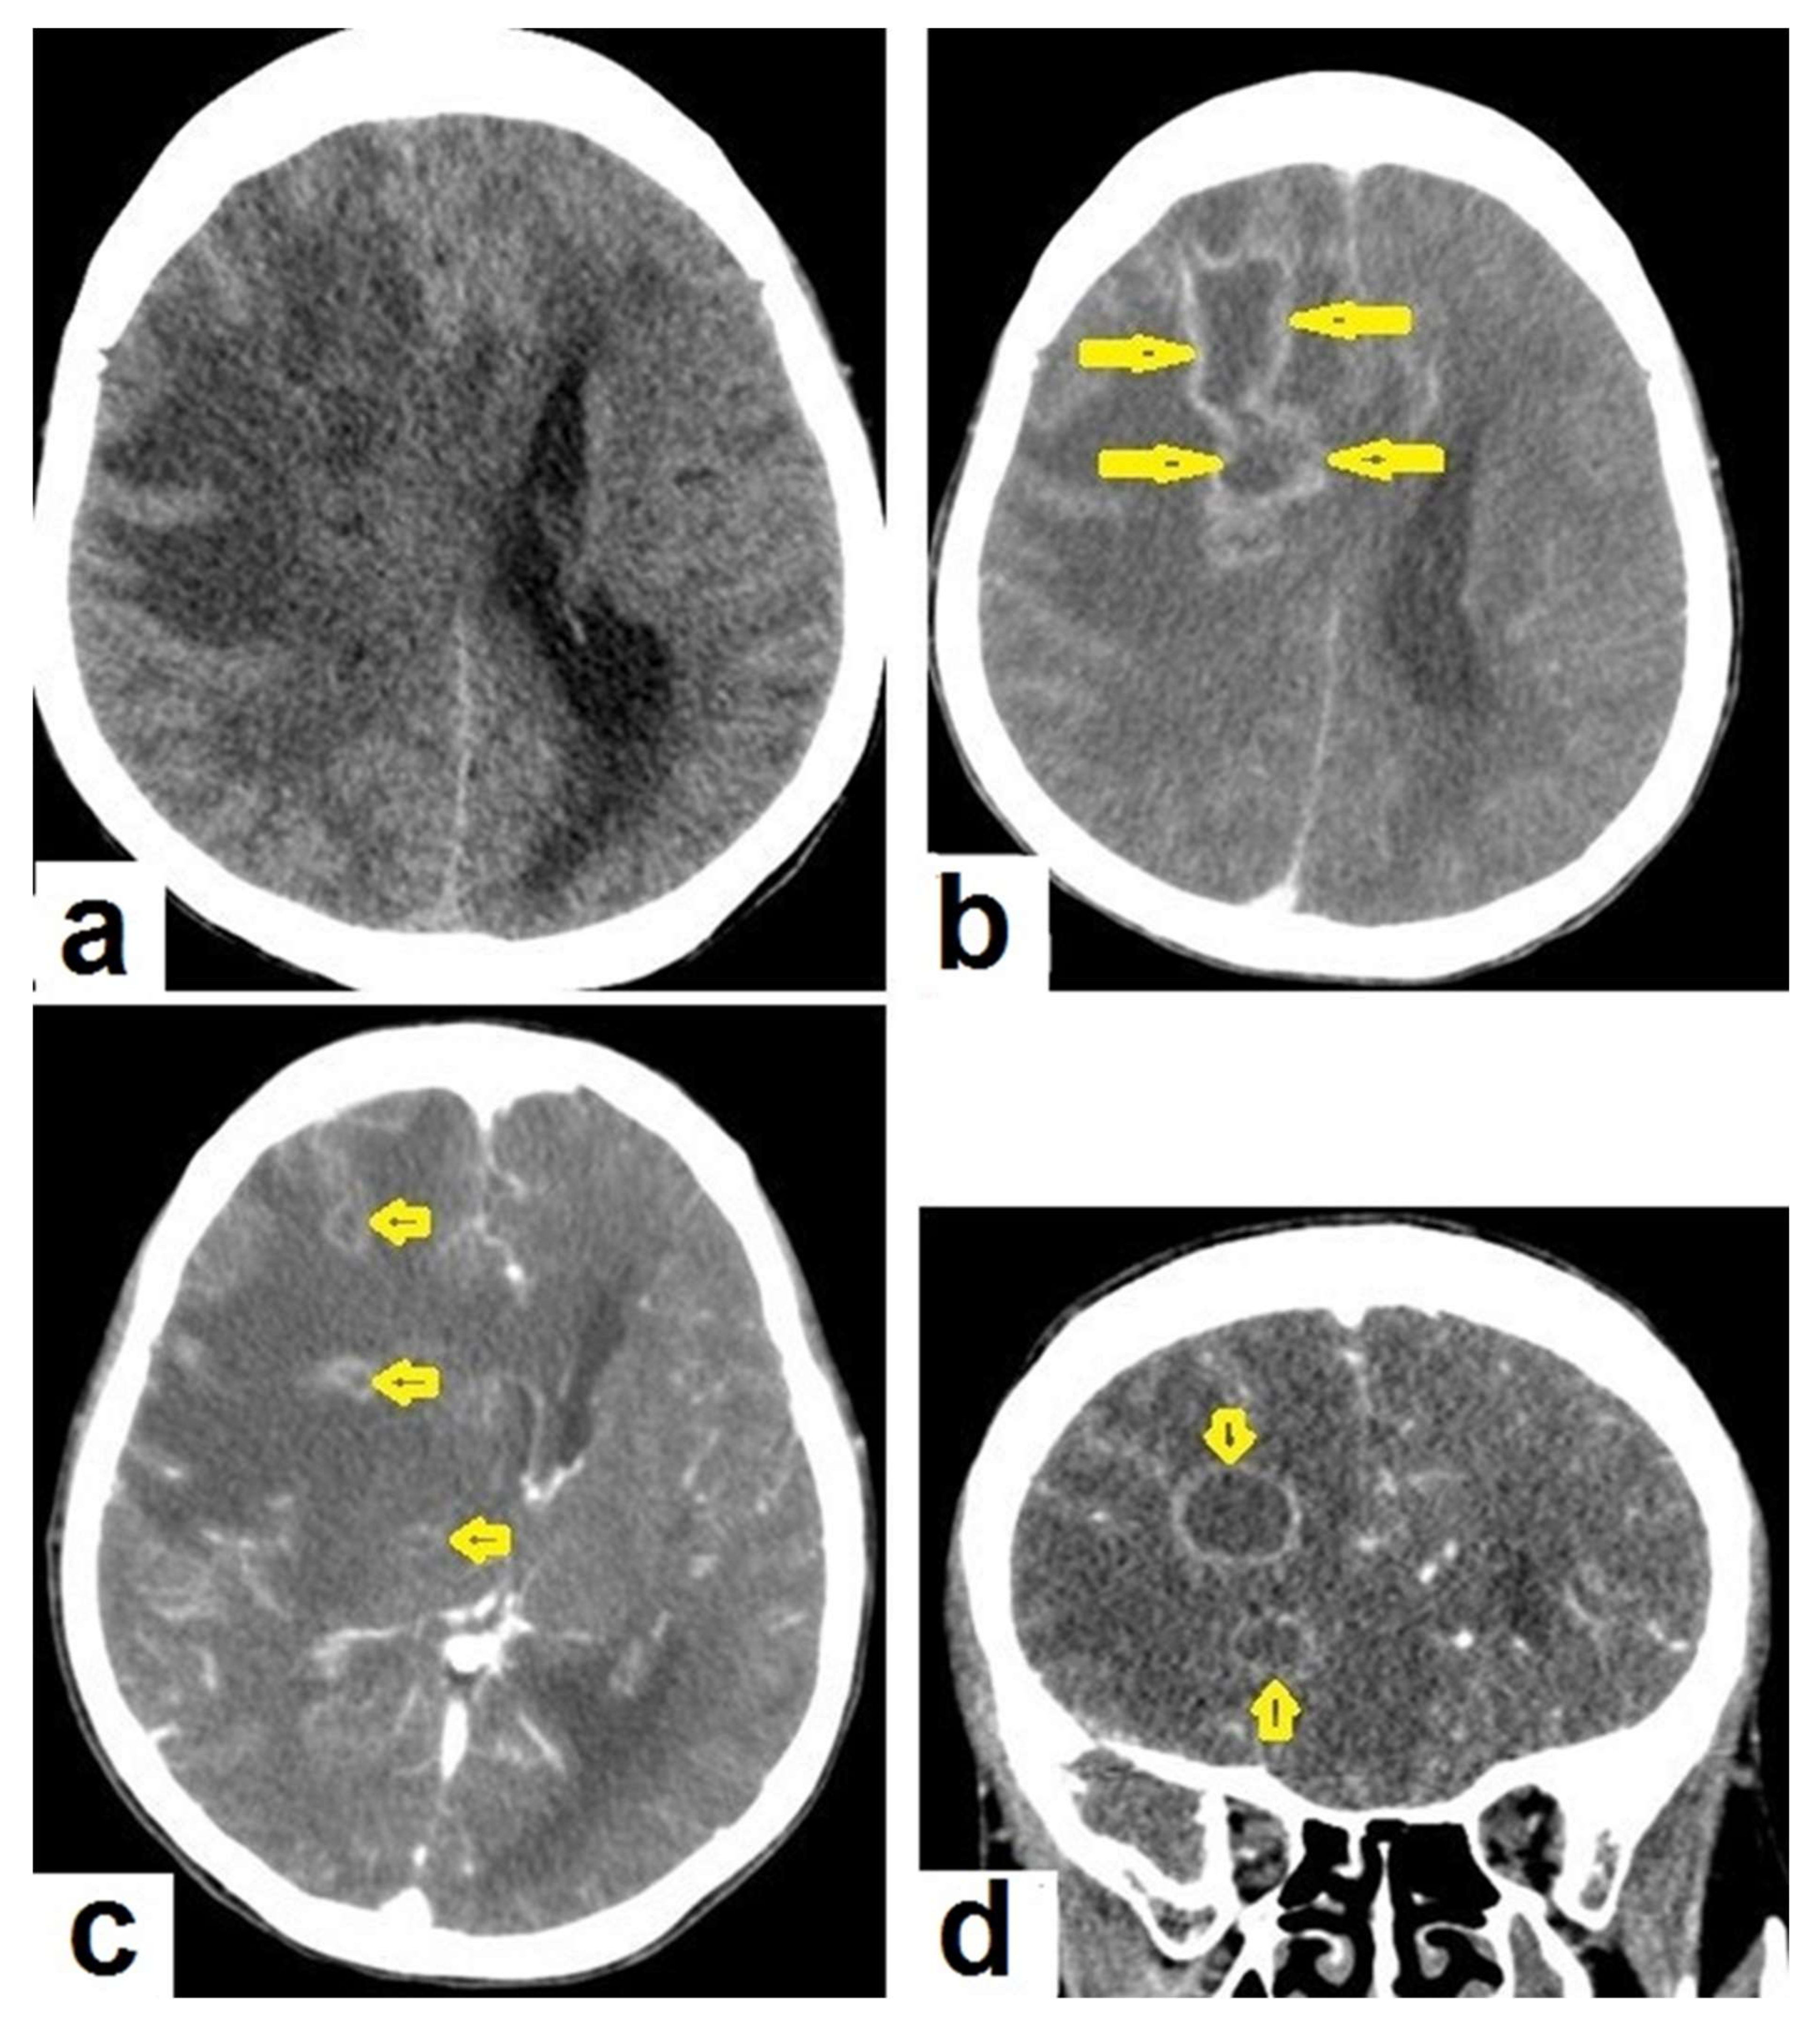

Figure 15. Tuberculous abscesses and tuberculomas in a 70-year-old woman with disturbance of consciousness and long history of headache. Selected axial computed tomography (CT) images of the brain (a) axial non-enhanced CT show significant vasogenic edema in the frontal and parietal lobes of the right cerebral hemisphere, with severe mass effect manifested as loss of the cortical sulci, total effacement of the right lateral ventricle and mild midline shift to the left side. (b) Contrast-enhanced CT (CECT) shows loculated rim-enhancing lesion centered in the right frontal lobe measures about 39 mm × 16 mm × 12 mm, suggesting cerebral abscess (arrows). (c) Axial CECT shows multiple ring-enhancing lesions in the right cerebral hemispheres and right basal ganglia (short arrows) suggesting of cerebral abscesses or tuberculomas. (d) Coronal CECT shows multiple ring-enhancing lesions in the right cerebral hemispheres (short arrows), suggesting cerebral tuberculomas or abscesses.

• Tuberculous abscesses (Figure 15, Figure 16 and Figure 17) are an infrequent pattern of brain TB, which are present in immunocompromised and elderly patients. They occur either due to the progression of cerebritis or the liquefaction of tuberculoma. On a brain CT, it occurs as a low density area with ring enhancement after contrast administration and the surrounding low density area of edema. On a brain MRI, it appears as a circular or elliptical area of low intensity with ring enhancement after contrast administration and surrounding low intensity area of edema on T1WIs and high intensity area with a high intensity surrounding edema. Tuberculous abscess is a difficult differential diagnosis of a pyogenic abscess, pilocystic astrocytoma, and other cystic lesions. MR spectroscopy may help in differentiating tuberculous from a pyogenic abscess [27,33].